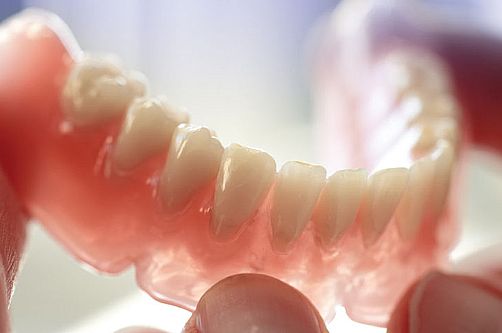

Prostheses can be total and partial. Total prostheses are created when all teeth are missing, whereas the solution for patients with a small number of preserved teeth is partial prostheses. A partial prosthesis is attached to the remaining teeth with small hooks and attachments (buckles or fasteners) and they can be acrylic or skeletal (also called wisil dentures). A partial acrylic prosthesis is completely made from acrylate and attached to the remaining teeth with wire hooks, so it is less resistant than a skeletal prosthesis. For that reason, it is less used, but its advantage is the cheaper price. A partial skeletal (wisil) prosthesis is a better solution because of the metal skeleton that provides more resistance and greater comfort ensured by the smaller part of the prosthesis leaning on soft tissues (the palate, sublingual region). Thus, the feeling of a foreign body is masked. Its advantage is also the attachment to the remaining natural teeth with the use of more precisely made cast hooks, which ensures considerably better stability in the mouth. Instead of hooks, attachments can be used to form a much better connection to the surrounding teeth.